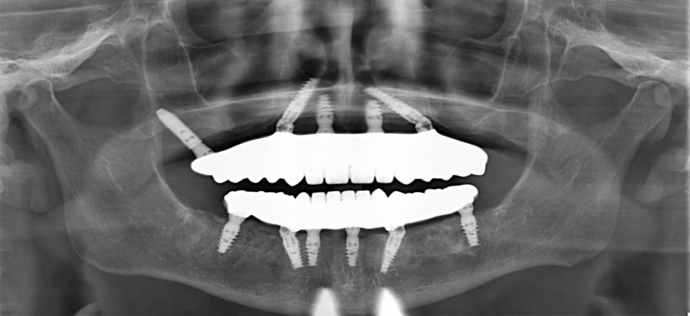

This busy professional unfortunately had lost all his teeth and then had implants placed for snap on dentures. The implants started failing after a few years and experienced bone loss. Patient was previously told my multiple dentists that he was not a candidate for dental implants. Patient was always unhappy with his snap on dentures and desired a permanent solution. The old implants were removed and Dr Bidra placed new implants in the upper and lower jaw and installed permanent teeth in the same day. After 4 months of healing, new zirconia permanent teeth were installed.

Procedures : extractions, failing snap on dentures, new implants, All on 4 , Teeth in a day, no bone grafting and full mouth reconstruction with monolithic zirconia bridges.